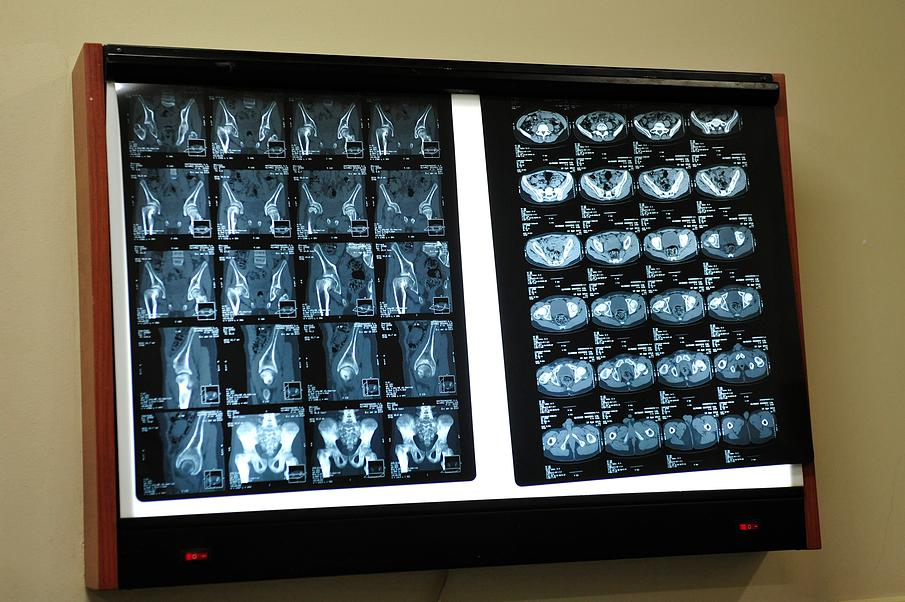

We now have photos!